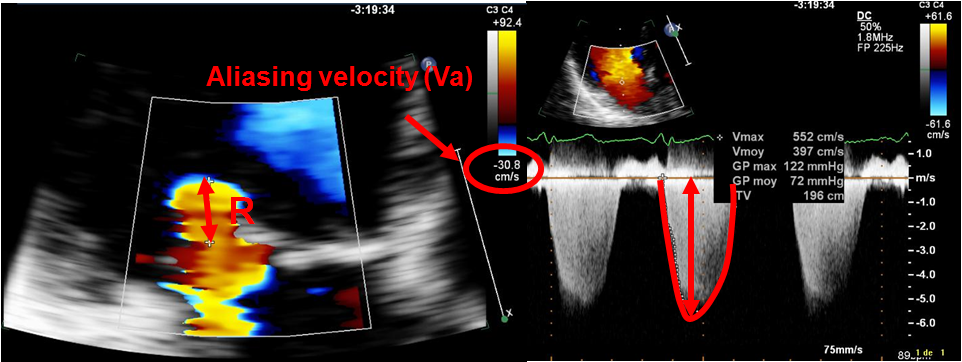

The symptoms and severity of the mitral valve regurgitation differ from patient to patient. This reduces the amount of blood that is pumped out to the body. Life Expectancy of People with Mitral Valve Regurgitation Types of Mitral Regurgitation: Primary: mitral regurgitation due to an pathologic problem with the mitral valve apparatus (leaflets, papillary muscle, chordae tendonae, and annulus); Secondary: functional mitral regurgitation due to diseases of the ventricle and/or atria, which cause dilation of the valve annulus, and malcoaptation of the leaflets.